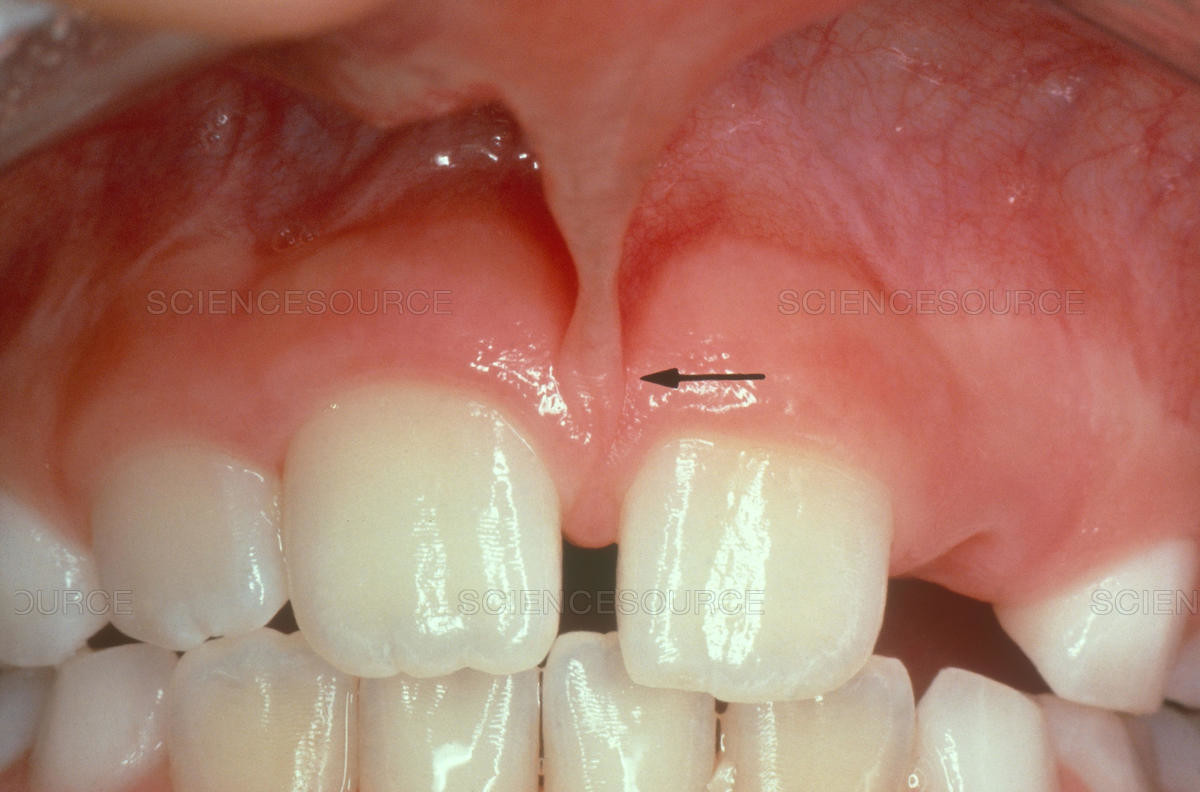

Frenulum In The Mouth

What Is A Frenum (Frenulum)?

In our mouth, most people have two groups of tissue called frenums found in and around the gums and teeth. It is a piece of really soft tissue that appears as a thin line between the gums and lips. You can find it on the top and the bottom of your oral cavity. There’s also a frenum that extends along the bottom of the tongue and connects to the bottom of the mouth just behind the teeth. Different people have different frenums. It can vary in length and thickness.

Labial frenum – This type of frenum is placed in the front of your mouth between the upper lip and gum. His counterpart is positioned between the lower gum and the lower lip. If there is an issue with this type of frenum, it can change the way your teeth grow in and can influence your dental health. Particularly it can pull your gums away from a tooth revealing the root.

Possible Problems With Frenum

The main purpose of a frenum is to give the lower and upper lip, as well as the tongue proper support and more stability in your mouth. If you suffer from an oversized frenum, it can lead to various problems that can affect your teeth, gums, and mouth.

· disruption of the healthy growth of your upper two front teeth, which may cause a gap

· the gap formed between front teeth

· receding of gum tissue away from the root of the teeth and revealing the tooth root.